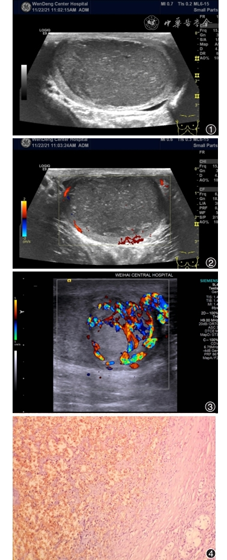

病例一,男,53岁,以双下肢静脉曲张来诊,主诉左侧睾丸肿大1年,偶有下坠感,误以为精索静脉曲张所致。查体,左侧睾丸肿大,触诊质硬,扪及睾丸表面光滑,无触痛,阴囊根部未触及曲张精索静脉,附睾及精索触诊阴性。超声所见:左侧睾丸增大,大小约5.3 cm×4.4 cm×3.1 cm,睾丸实质边缘见环状均质等回声睾丸组织,宽约0.2 cm,其内代之以大小约4.7 cm×4.1 cm×2.8 cm类实性低回声占位(图1),边界清晰,形态规则,回声不均匀,其内见多发点状及短条索状强回声,呈散在分布,内部未显示明显血流信号,周边可见条状血流信号,部分呈绕行血流(图2)。超声提示:左侧睾丸类实性占位,不除外精原细胞瘤。患者于全麻下行左侧睾丸探查及左侧睾丸切除术,切除睾丸组织7.0 cm×4.5 cm×4.0 cm,切面灰黄,质软,病理诊断:左侧睾丸表皮样囊肿。

病例二,男,26岁,主因右侧睾丸增大半年,自述曾于1年前有过外伤史,当地医院诊断炎症,未复诊。查体,右侧睾丸肿大,触诊质硬,扪及睾丸表面光滑,无触痛及抬举痛。超声所见:右侧睾丸增大,中下部形态不规则,可见大小约2.4 cm×2.2 cm×2.1 cm实性等回声占位,边界清晰,部分略呈外凸,内部回声不均匀,隐约见短条索样低回声,内见丰富血流(图3)。余右侧睾丸组织回声均匀。超声提示:右侧睾丸实性占位,良性病变可能性大。行右侧睾丸肿瘤切除术,术中见右侧睾丸结节性肿物一枚,体积3.0 cm×2.5 cm×2.5 cm,切面呈紫红色,呈网格样表现,内部填充以血凝块及淤血,质地较软,见少量短条状血栓样组织。术中冰冻病理诊断为右侧睾丸血管瘤,术后病理诊断同前,符合海绵状血管瘤(图4)。